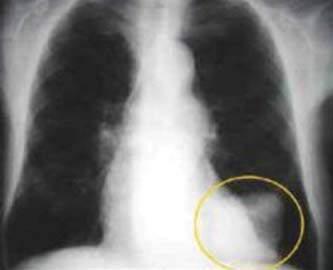

Рис.

уражаючи органи дихання (грип, аденоінфекції), травну (гастроентерити, гепатити) та нервову (поліомієліт, енцефаліти) системи, шкіру та слизові оболонки (кір, герпес, папіломи, вітряна віспа), пригнічують імунні реакції організму (СНІД), призводять до ракових захворювань (рис. 27, 28). Негативний вплив вірусів

оболонки дихальних шляхів. Геном утворений вісьма одноланцюговими молекулами РНК.